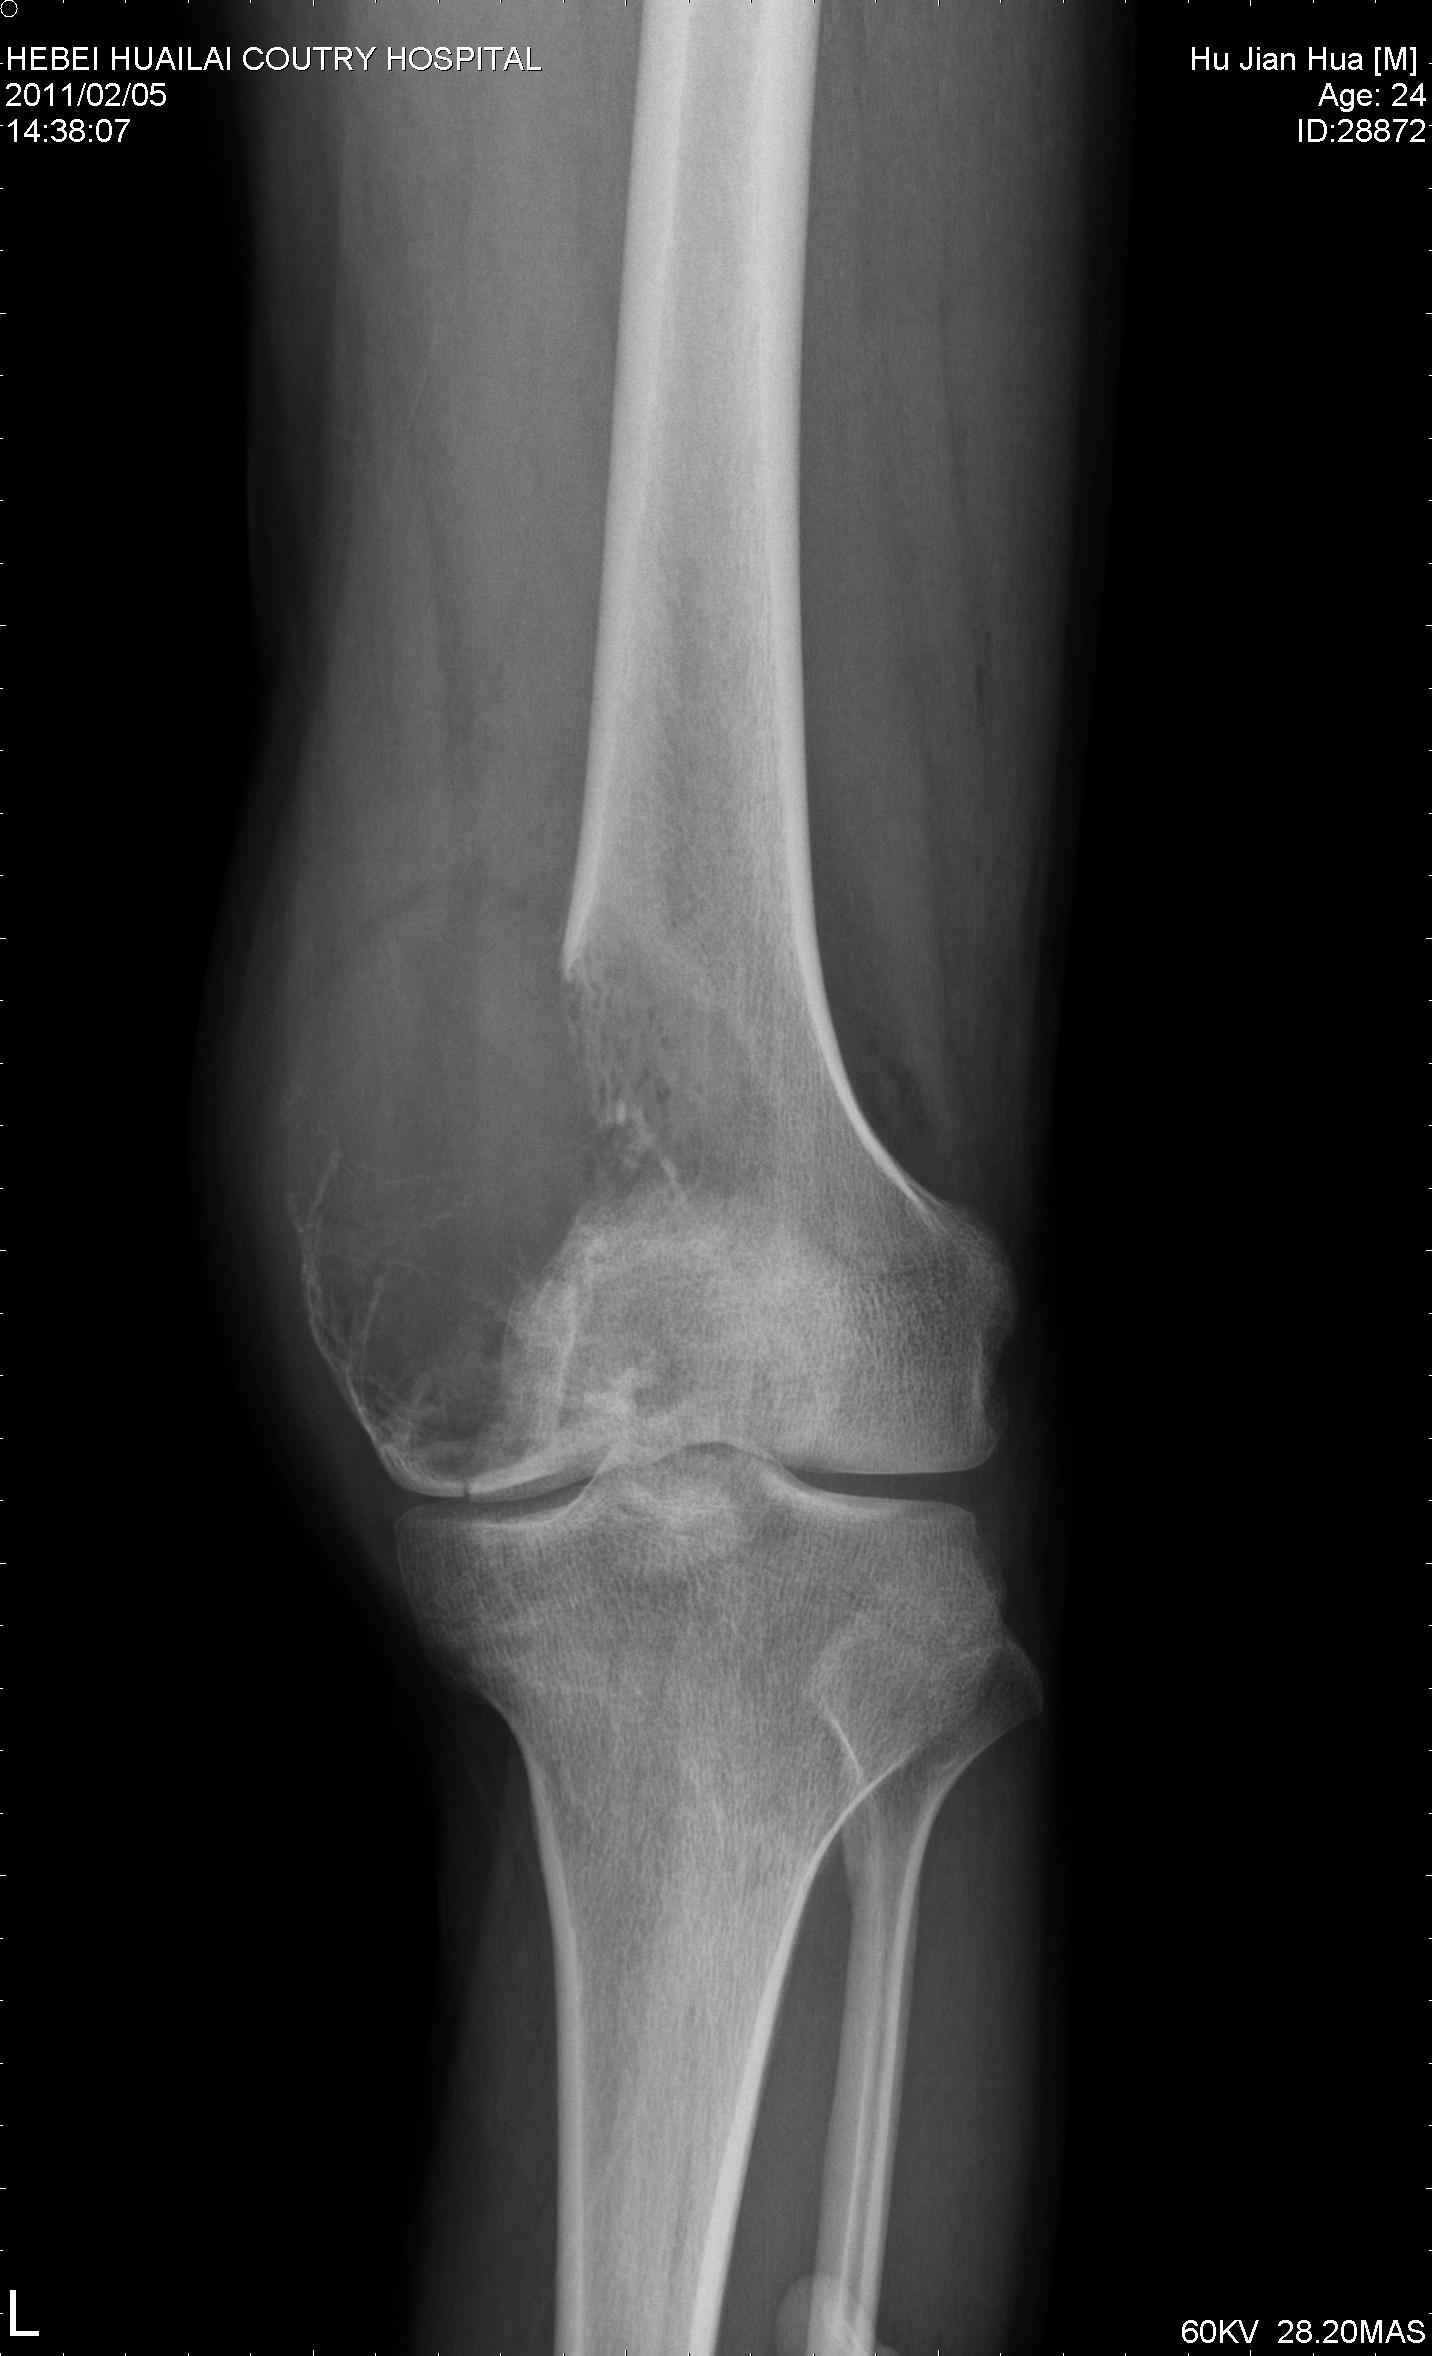

骨巨细胞瘤

患者24岁,左膝疼痛半年余就诊,拟诊左股骨远骨肉瘤,请各位同仁不吝赐教

病例结果:病人已在301医院接受膝关节置换手术,病理结果为